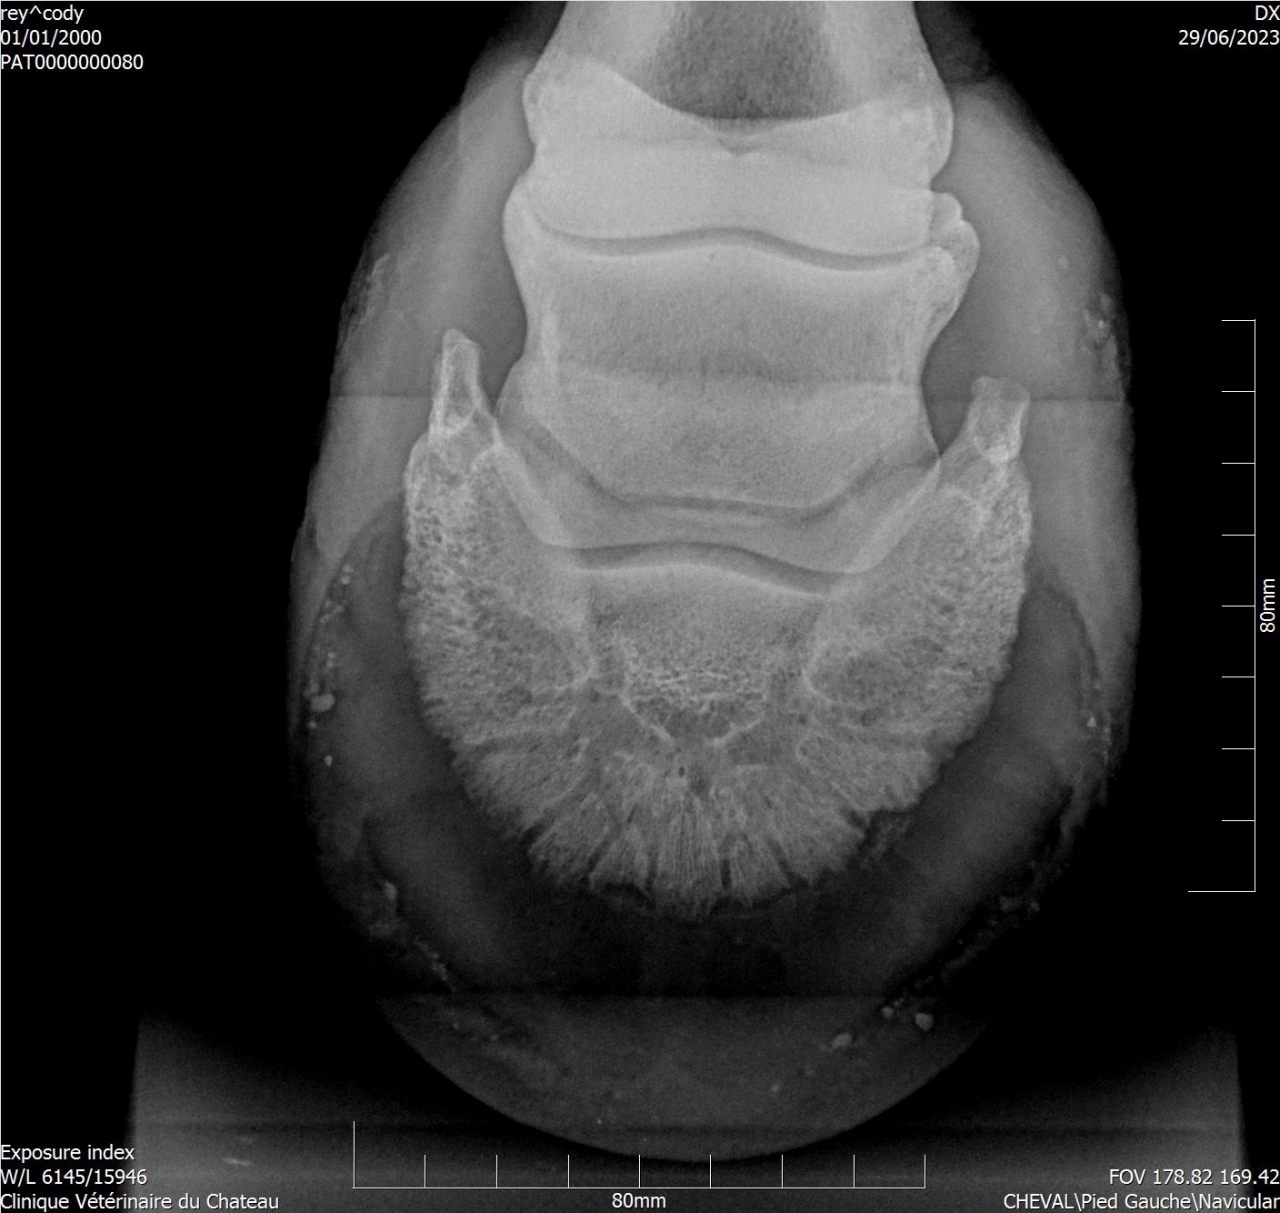

Par goss_de_panloup : le 02/11/24 à 20:39:15

| Dire merci | Aucun des vétos consultés n’a été capable de donner une explication à la boiterie et à la douleur au ferrage ... Voici des radios de l’année dernière : ![]() ![]() Si quelqu'un a une bonne adresse de spécialiste en Isère je prends. |

| Dire merci | Tu as une radio LM par hasard ? |

| Dire merci | Un cheval qui bosse pas, qui a juste 10 ans et qui a une locomotion dégradée selon les jours, ça pue l arthrose précoce, le naviculaire ou chais pas quoi. Il te faut un vrai bilan ds une clinique qui sait faire les radios et échos et qui sait les lire |

| Dire merci | Voir aussi que beaucoup d'américains ont des problèmes de pieds. Je me dis qu'en allant faire un bilan locomoteur plus poussé dans une clinique, tu auras aussi plus de gens d'avoir des vétos qui connaissent ces problèmes |